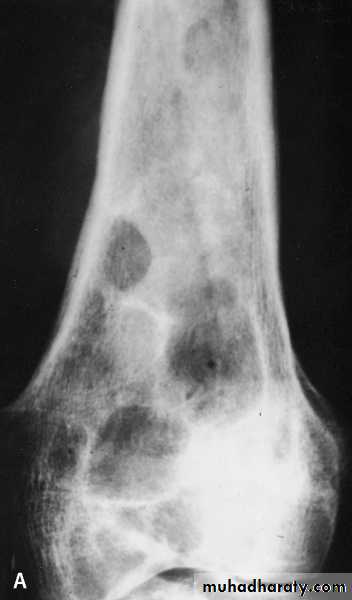

osseous H. cyst :

When the embryo of E. granulosus reaches bony tissues it will develop to osseous hydatid cyst.The larva grows as a protoplasmic stream that erodes the cancellous tissues and lead to multiple bone fractures.

It is occur in the ends of long bones and pelvic arch

sterile never produces brood capsule and protoscolices with little or no fluid and no fibrous capsule.